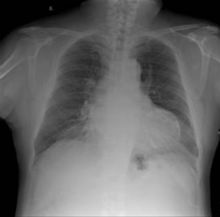

2.心臟增大,心包積液、心力衰竭的表現和心電圖異常。

3. 胸部x線片,超聲心動圖,心電圖。